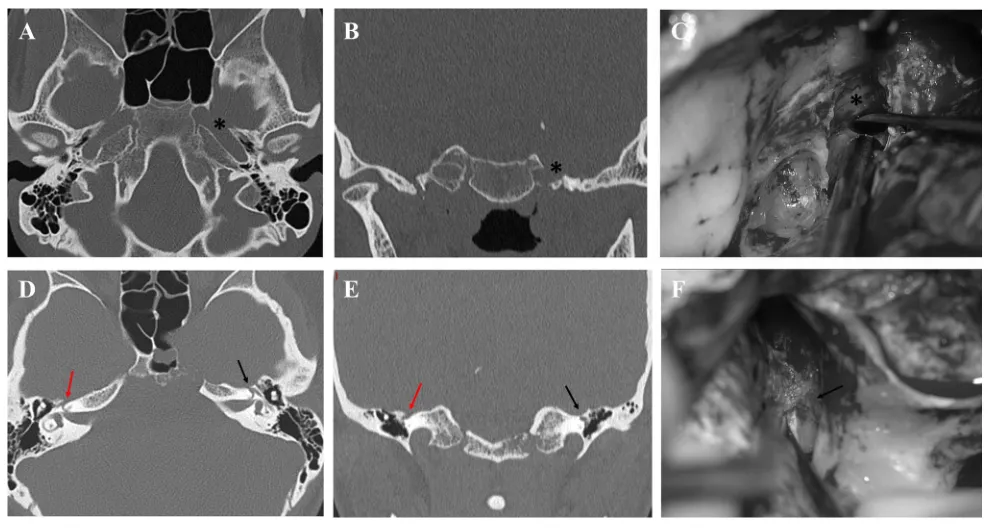

在着手剥离硬脑膜前,轴位和冠状位CT扫描必须先行检查中颅窝底的骨质状态。首要任务是确认中颅窝底是否存在普遍性隆起或凹陷。尤其需要警惕的是岩骨段颈内动脉或膝状神经节上方的骨质缺损——忽略这一细节极易演变为导致神经功能受损的手术事故。

具体而言,若遗漏了岩骨段颈内动脉上方的骨质缺损,在Kawase菱形窝显露及岩尖磨骨过程中可能引发难以控制的大出血。此时将三叉神经第三支(V3)稍作前方移位,有助于辨认出颈内动脉骨质缺损的具体范围。同理,当膝状神经节未被骨质完全覆盖时,硬脑膜剥离过程中存在术后面神经麻痹的风险,极端情况下若发生膝状神经节撕脱甚至可导致永久性功能丧失。此外,棘孔与卵圆孔融合的罕见解剖变异也会增加处理脑膜中动脉时损伤V3的可能性。

图5. 中颅窝骨质缺损。CT显示左侧岩骨段颈内动脉(*)存在术前骨质缺损(A, B),该患者术中证实了岩骨段颈内动脉上方无骨质覆盖(C)。CT揭示右侧中颅窝底在膝状神经节上方存在骨质缺损(红色箭头),而相应的左侧(黑色箭头)无骨质缺损(D, E)。术中图像证实膝状神经节(黑色箭头)上方无骨质覆盖(F)。